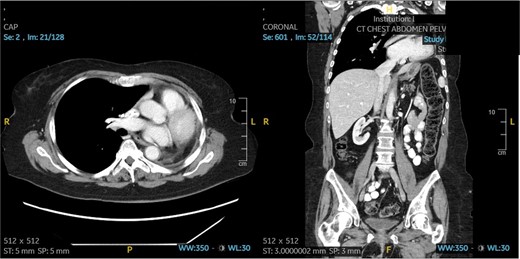

The patient underwent a muscle sparing left thoracotomy, extrapleural intrapericardial left pneumonectomy, and serratus anterior muscle flap to the bronchial stump. The operation was challenging as the fungal mass was densely adherent to the chest wall and all hilar structures, requiring isolation of the pulmonary artery intrapericardially. A serratus anterior muscle flap was then placed over the bronchial stump. Estimated blood loss was 1000 mL intraoperatively. The patient did well post-operatively, only required transfusion of 1 unit of packed red blood cells on postoperative day 3 and was discharged on postoperative day 5. She was doing well without dyspnea, and free of fungal disease on her most recent follow-up 18 months after her operation. Follow-up chest CT scan can be seen in Fig. 3.

Patient 2 post-operative CT scan showing complete resection of disease and expected post-operative anatomical changes, including leftward deviation of mediastinum and hemidiaphragmatic elevation.